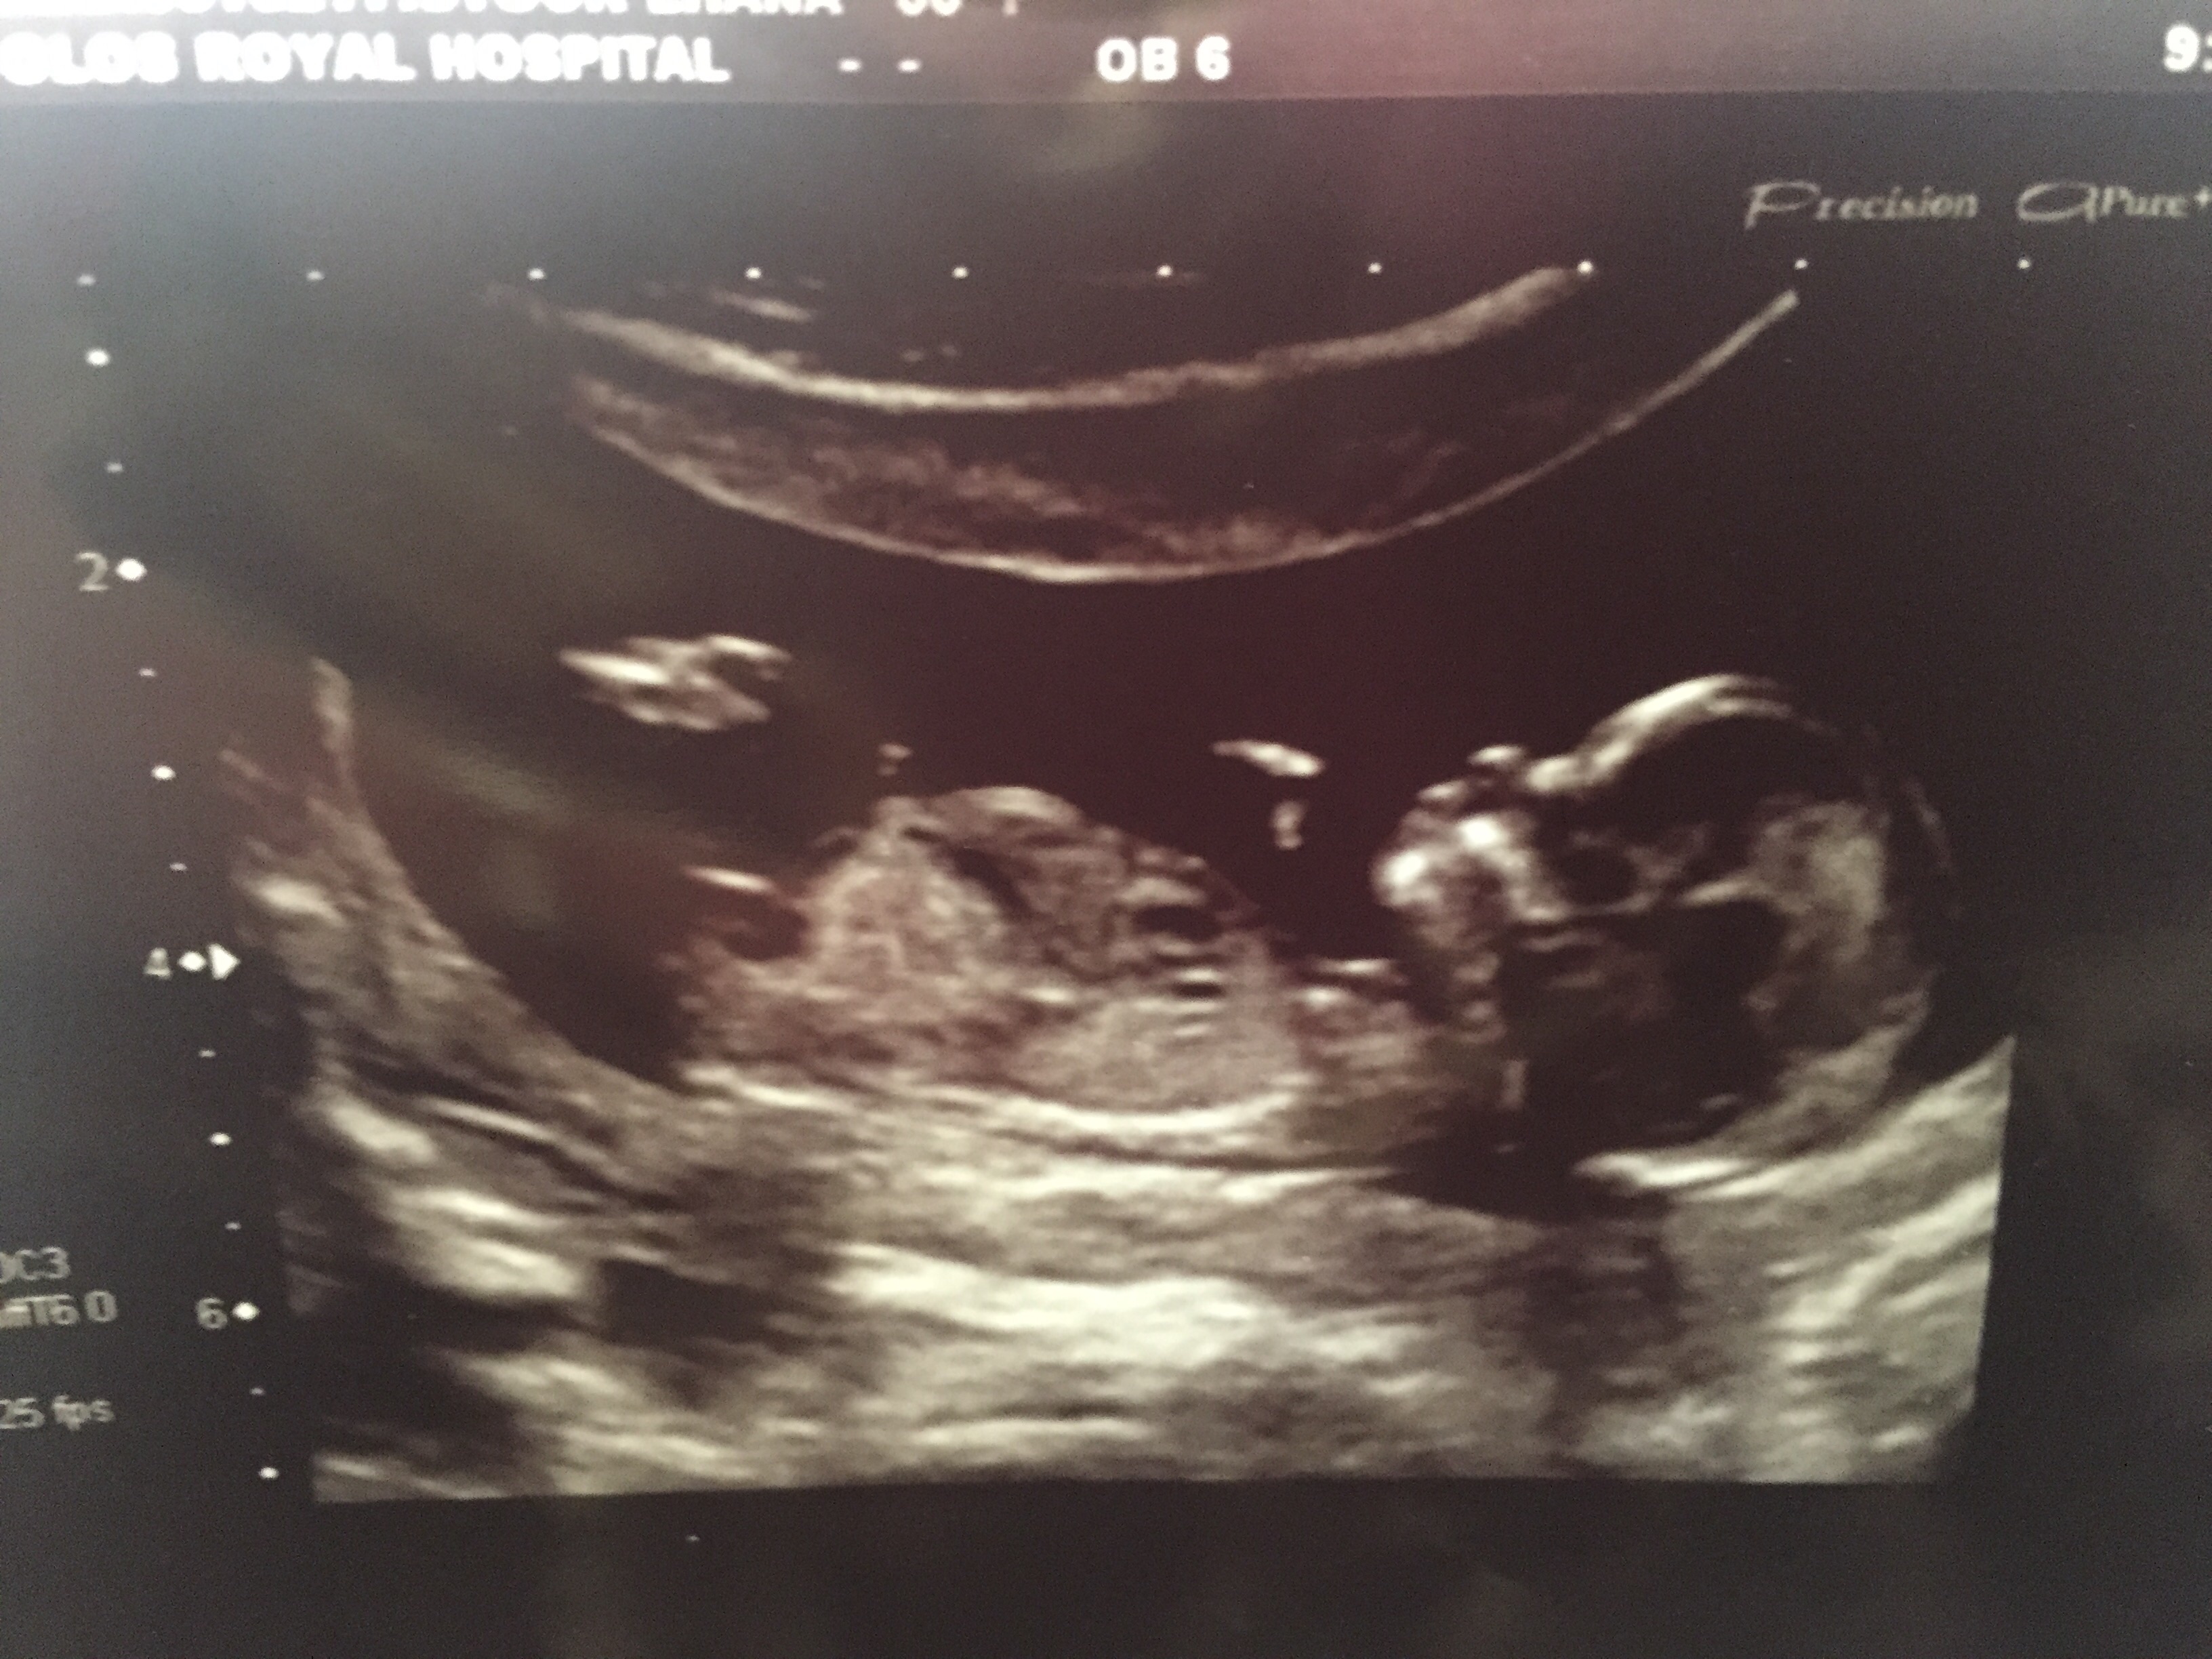

Boy or girl!? 12 week scan - ultrasound gender prediction ...

Boy or girl!? 12 week scan - ultrasound gender prediction ... from imageserve.babycenter.com

Whats the accuracy of sonographic determination of fetal gender study. Full text ultrasound measurement learning of fetal sex. Biomedical papers of the medical faculty of the university palacky, olomouc, czech republic (2012) 5. Early baby gender predictor explained 2019. Updated on october 18, 2008. It's the grainy, black and white image that makes it all seem so real and we've found four. Gender confirmed by harmony test! 12 weeks 5 days ultrasound/ gender reveal.

Ramzi and nub theories, nub and skull.

My baby boy in 12 week scan | gender prediction week 12 ultrasound. Ramzi and nub theories, nub and skull. Nub method has very high accuracy when measuring angle of nub compared to spine! Ultrasound imaging performed in the 11th and 12th weeks of pregnancy for fetal gender identification identified the fetus either as a girl, a boy, or as a the sagittal sign for sonographic prediction of fetal gender in the early second trimester is described and its sensitivity and accuracy evaluated. You must also remember that a nub analysis before 12 weeks of pregnancy, especially for babygram can give you a reliable prediction of your baby's gender. Ultrasound and gender detection gender is determined by visually inspecting the ultrasound several studies have been conducted to determine the accuracy of gender prediction at different at 12 weeks, 99% of male gender predictions were correct, and 91% of female predictions were. But if baby is only measuring 12 weeks exactly it's still early and there is still time to change. Check out my designer online children's. Experts at babygram use the nub theory to thoroughly analyze your ultrasound. 12 week ultrasound for gender reveal. 12 week ultrasound gender prediction mp3 & mp4. Biomedical papers of the medical faculty of the university palacky, olomouc, czech republic (2012) 5. My mom bawled her eyes out and you can hear.